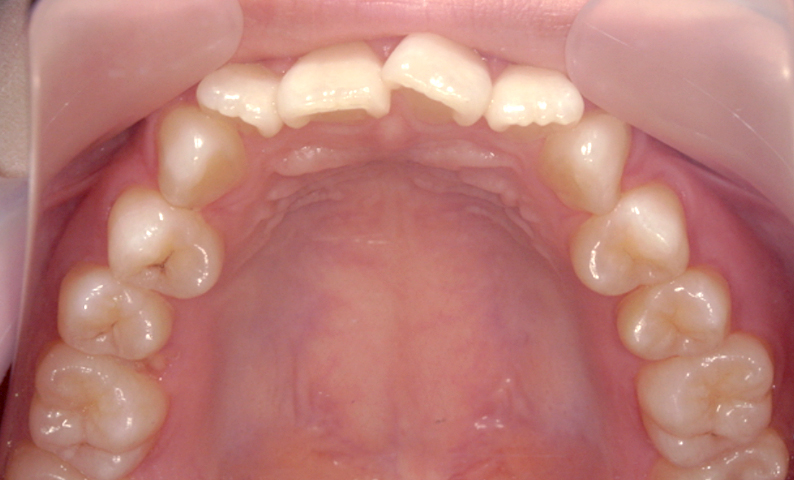

症例_004 上下顎の部分矯正

治療期間:8ヶ月金額:54万円+税女性前歯のガタガタ捻転歯